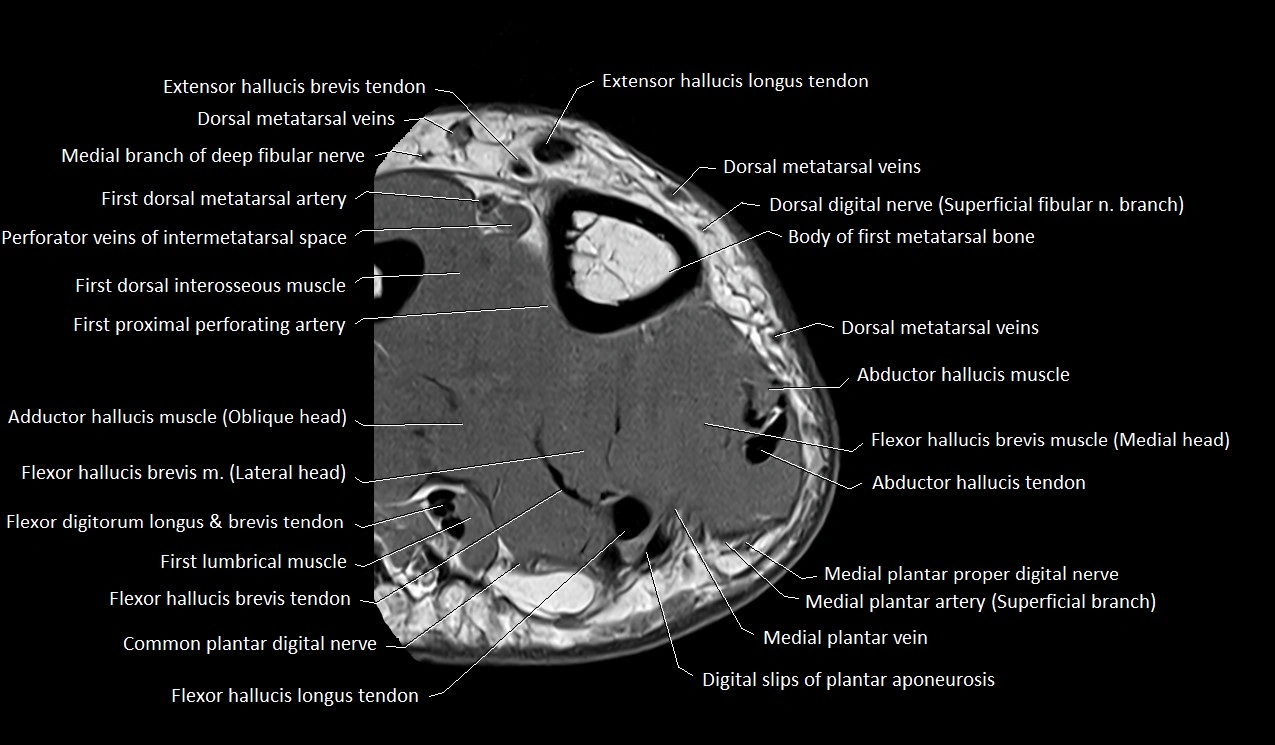

MRI image

image